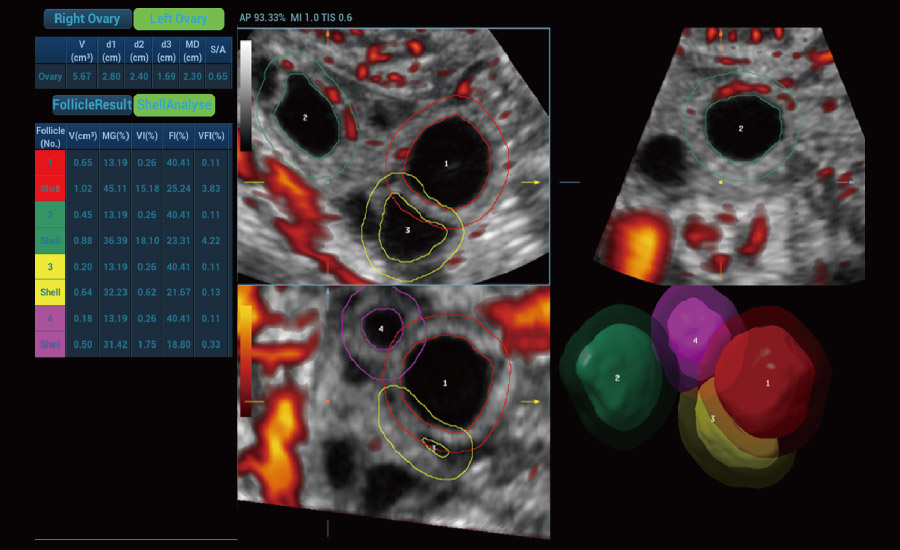

UMA (Ultra-Micro Angiography)

The innovative technology breaks the bottlenecks of traditional Doppler imaging. With ultra-high spatial resolution and flow sensitivity, it allows detecting super-subtle and super-slow flow perfusions, thereby extending the clinical application of qualitative and quantitative ultrasound evaluation in fetal brain, kidney, placenta, endometrium, ovary, etc.

3D UMA - perifollicular blood flow

Scenario-oriented Full-stack Intelligence

Combining advanced algorithms and domain-specific knowledge, the innovative Smart Scene solution enables auto identification of tissue characteristics and provides organ-specific diagnosis with full-stack intelligence. Based on auto scenario identification, the solution not only realizes smart 2D scanning with auto settings and measurements, but also delivers 3D full-stack intelligence in every step from volume imaging optimization to the difficult 2D plane acquisition, and quantification throughout whole procedure. It helps a lot in reducing the dependency on clinical skills, while increasing diagnostic accuracy, confidence and efficiency.

Fertility